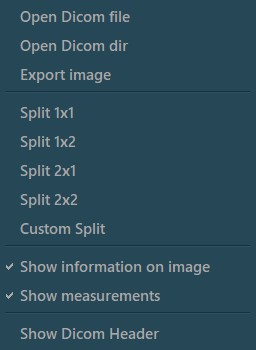

Open DICOM files in the active Viewer tab

Customize the Viewer grid

View DICOM file information by accessing the DICOM Header